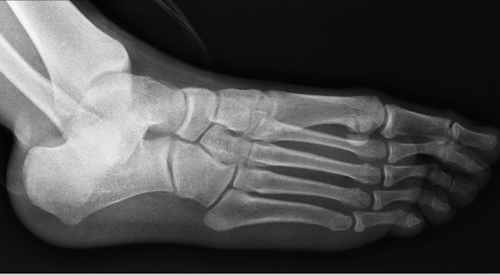

El proceso de osificación del ser humano sigue una secuencia de acontecimientos fisiológicos identificables en la estructura ósea del esqueleto, tanto en el examen morfológico directo, como en la observación de estos mediante radiografía (Figura 1). En la práctica clínica es importante conocer con precisión la edad ósea de individuos en crecimiento para evaluar su estado de desarrollo, y así establecer una correspondencia con la edad cronológica del sujeto3.

Figura 1. Radiografía oblicua de los huesos del pie.